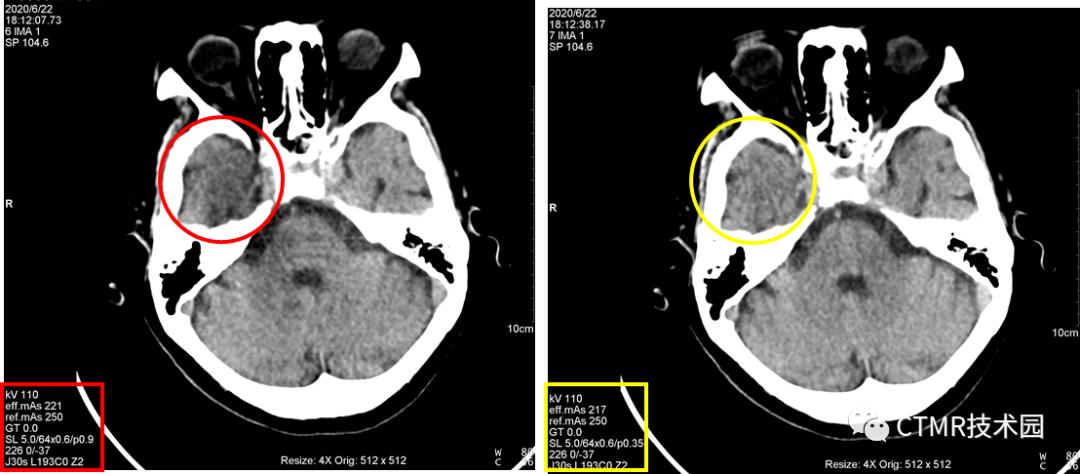

我们有一台西门子 SOMATOM Perspective 64 CT,从装机到现在四五年了,颅脑螺旋扫描条件扫描颅脑,在右侧颞区始终有“暗区”伪影,十分诡异。

我们先不去猜测什么原因导致的,先说说经过。诊断医生一直嫌弃颅脑螺旋扫描图像质量差,还有伪影。因此,一般也会使用颅脑轴扫条件。(关于颅脑 CT 平扫到底用轴扫还是螺旋扫描?当然是轴扫效果好,但是日常工作中,病人量巨大,且各种病人情况不尽相同,普诊、急诊、能配合的,不能配合的等等,再结合现在探测器性能都非常好,那么好多都偏向使用螺旋扫描,而且螺旋扫描对于外伤的病人看骨折重建薄层、MPR等都非常有利。轴扫时间长,如果病人再不配合很容易出现运动,剪薄层效果也不如螺旋好)反馈给厂家,也来工程师检修了,空气校正什么的都不能解决,最后结论说是检查床有偏移,检查时需手动往一侧推下床板。我对这个结论一直持怀疑态度,也试过,即使推检查床板也还是会有伪影。那么这个伪影到底哪来的?一切还需从检查条件中查找。下面我们来看下 检查条件 Protocol(HeadRoutine) 具体扫描参数:

上周我在此机器值班,因为此伪影一直在我脑子里存留,平时在上 Philips Brilliance 64 CT 时,注意观察了下它扫描颅脑的螺距,非常小,可供选择的范围很小,最大可选 0.399。飞利浦的机器比较好的一点就是,它固化了 Scan type,不同的扫描部位/检查方法定义不同的 Scan type,那么在 Brain 扫描类型下,再进一步限制 Collimitation,螺距,Rotation time 等一系列参数,以期获得最佳的的图像质量。那么我就在此机器上尝试选用小螺旋扫描,最小可以改到 0.35,扫了几个病人,伪影完全消失!可以证明,在西门子这台机器上采用大螺距扫描是不合理的,应当也使用小螺距扫描。而且采用小螺距 DLP 还降低了,那么可以进一步增大 QRM,以期获得更好的图像。

而且选用 0.35螺距 eMode 是绿色;如果用 1.1 螺距,那么 eMode 是黄色;如果应用 Adjust,eMode 也变成绿色,且此时当前病人配给的螺距为 0.9,那么它好吗?其实扫描出来的图像大多还是有伪影(从本文开头贴的图片中,有好几个都是 Adjust 后匹配螺距扫描出来的伪影图像)。